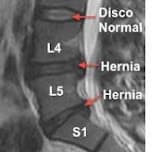

LA L4-L5.Hay muchísimas personas que sufren de dolor de "Rabadilla".- Así lo dicen en algunos países, en España lumbalgias, tambièn los ...